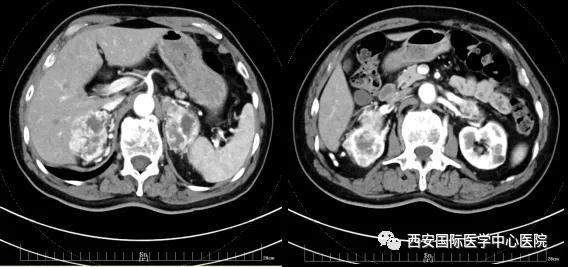

今年七十五歲的患者,來自陜西省商洛市,四月前因腰背部疼痛就診于當?shù)蒯t(yī)院,行CT檢查發(fā)現(xiàn)“右腎、雙側(cè)腎上腺占位,前縱膈淋巴結(jié)腫大,雙肺多發(fā)結(jié)節(jié)、胸椎骨質(zhì)破壞,考慮轉(zhuǎn)移瘤”。為進一步診斷治療,患者的兒子帶他來到西安某三甲醫(yī)院,查泌尿系CT提示“右腎占位性病變,多考慮腎癌,雙側(cè)腎上腺多發(fā)轉(zhuǎn)移灶,腹膜后多發(fā)腫大淋巴結(jié)”;行穿刺活檢提示“腎透明細胞癌”;并給予患者口服靶向藥物的治療方案。

自四月份至今,患者一直口服靶向藥物治療(阿昔替尼5mg 2次/日),期間無不良反應(yīng),目前腰背部疼痛癥狀也有所緩解,復(fù)查影像學(xué)資料提示瘤體較前縮小,腫瘤完整切除的可能性明顯提高;而且患者的兒子也是一名外科醫(yī)生,所以他更想為父親完成后續(xù)的手術(shù)治療。

患者一家慕名前來到西安國際醫(yī)學(xué)中心醫(yī)院找到楊增悅教授。楊增悅教授仔細看完患者的之前的影像學(xué)及病理資料后,診斷為:右腎透明細胞癌(T4N1M1);并安排他住院。而后,主管醫(yī)生及時為他完善了術(shù)前檢查及評估。7月15日,在麻醉手術(shù)中心柴偉主任、王彬榮副主任、李娟護士長、李瑞剛護士長及全體麻醉手術(shù)中心團隊的有力保障下,成功完成了這臺“大”手術(shù)。